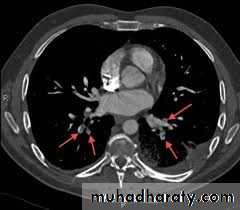

CT pulmonary angiography (CTPA)

It visualizes the distribution and extent of emboli in positive cases.

It may also prove alternative diagnosisSimultaneous visualization of femoral and popliteal veins for DVT improves sensitivity.

Can be performed safely in pregnant women (with foetal shielding).